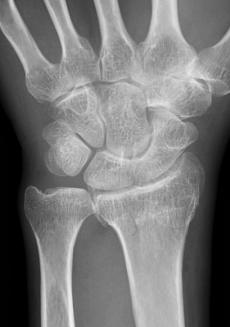

トモシンセシスはX線管の角度を変えながら撮影を行い、得られた複数の投影X線画像から任意高さの断層像を得る手法です。

単純撮影に比べ微細な骨折の描出に優れます。

データご提供:日本鋼管病院様